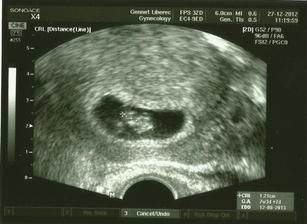

27.12.2012 UTZ bublinka má 1,21cm a v Gennetu už se s námi rozloučili